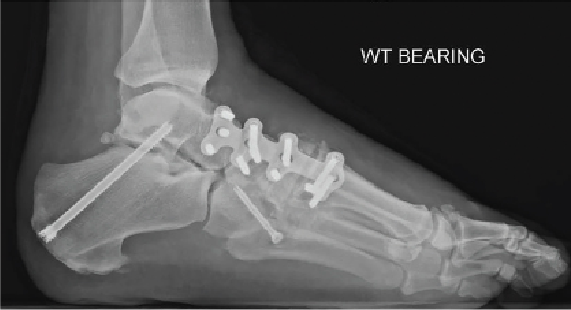

Medial column plating provides a strong fixation construct that we find especially beneficial in Charcot midfoot reconstruction. This plating technique bridges areas of weakened or grafted bone and can be anchored into stronger bone distally, proximally, and laterally. The addition of locking plates and screws provides an advantage to surgeons as the screw is attached to the plate rather than directly to the bone. This type of fixation is less dependent on the quality of the bone compared to conventional plates and screws, making it effective in softer osteoporotic bone. Bicortical fixation can further increase screw resistance to pull-out in this system. The current design of medial column plates consists of stronger, thicker plate constructs combined with the utilization of screws extending more lateral to encompass multiple bones. Of note, we prefer to use 4.0-mm screws and on average a length of 40 mm.

The surgeon may then attach the medial column plate after contouring the medial bone surfaces to accept the plate. It is vital that the plate spans not only the apex of the deformity but also extends proximally and distally to allow screw fixation into the stronger unaffected bones/joints, at times used as a bridge plate. A combination of locking and nonlocking screws can be utilized to fixate the reduction.

Additional implementation of prophylactic fixation is possible by inserting a transarticular subtalar joint screw percutaneously from the calcaneus into talus to stabilize the subtalar joint.